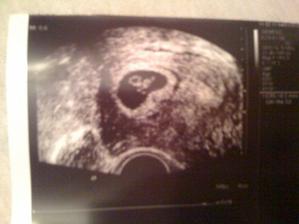

18.12.2009 sme sa dozvedeli ze cakame druhe babulko. na uzv som ho prvy krat videla a meralo 5milimetrov...